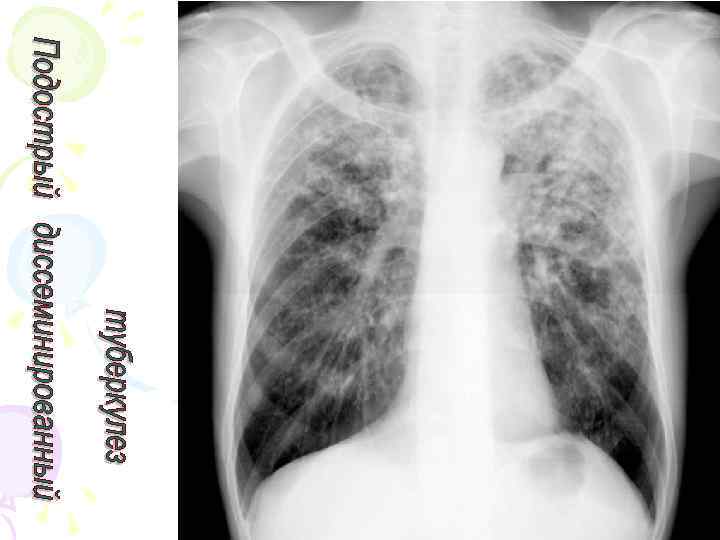

Рентгенологическая картина Спустя 10 -14 дней болезни появляются множественные мелкие / до 2 мм/ однотипные очаги на всем протяжении легких, создается впечатление о более массивной диссеминации в средних отделах. Очаги округлой формы, малой интенсивности, контуры нечеткие, часто расположены в виде цепочки вдоль сосудов. Сосудистый рисунок обеднен

Подострый диссеминированный туберкулез легких патоморфология • более или менее равномерная и симметричная диссеминация в обоих легких /хотя, может быть и односторонний процесс лимфогенного генеза/ • очаги крупнее (5 -10 мм), чаще, но не всегда, имеют однотипный характер, находятся в большем числе в верхних отделах легких, субплеврально, преимущественно продуктивный характер • очаги имеют тенденцию к слиянию • Могут возникать полости распада с тонкими стенками и без инфильтративного вала, т. н. " штампованные" каверны. Нередко они располагаются симметрично в верхних отделах обоих легких - "очковые" каверны или "симптом очков « • развиваются также лимфангиты, периваскулиты, перибронхиты, эмфизема

Рентгенологическая картина • множественные крупные / до 10 мм/ однотипные очаги преимущественно в верхних и средних отделах легких • Очаги округлой формы, малой и средней интенсивности, контуры нечеткие, часто расположены в виде цепочки вдоль продольных сосудов • Сливаясь, очаги образуют фокусы затемнения с участками просветления (распад) • При распаде в нескольких отдельных очагах формируются кольцевидные тени – штампованные каверны • При лимфогенной диссеминации очаговые тени с одной стороны, в средних и нижних отделах на фоне лимфангита, в корне кальцинаты